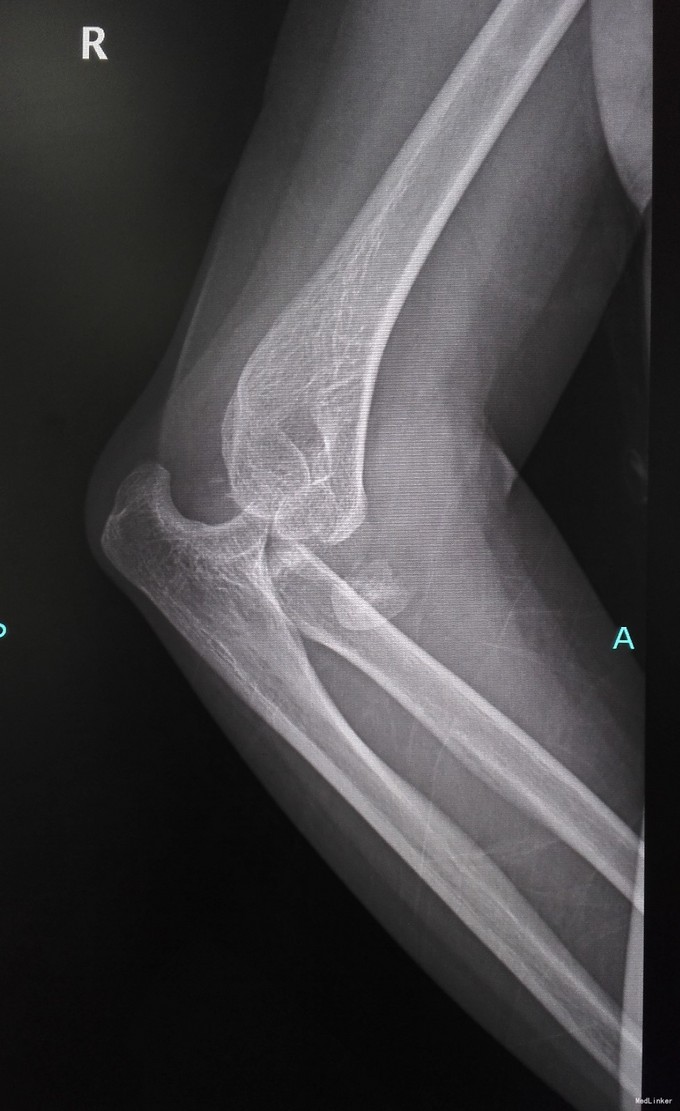

女性,67岁,车祸致右肘肿痛畸形1天入院

查体见右肘肿胀畸形严重,予以临时复位石膏固定,输液抬高消肿。

诊断为肘关节恐怖三联征(肘关节后脱位伴桡骨头和尺骨冠状突骨折),消肿后予以切开复位Wright桡骨小头假体置换,外侧副韧带修补,冠状突骨块小,未行固定。